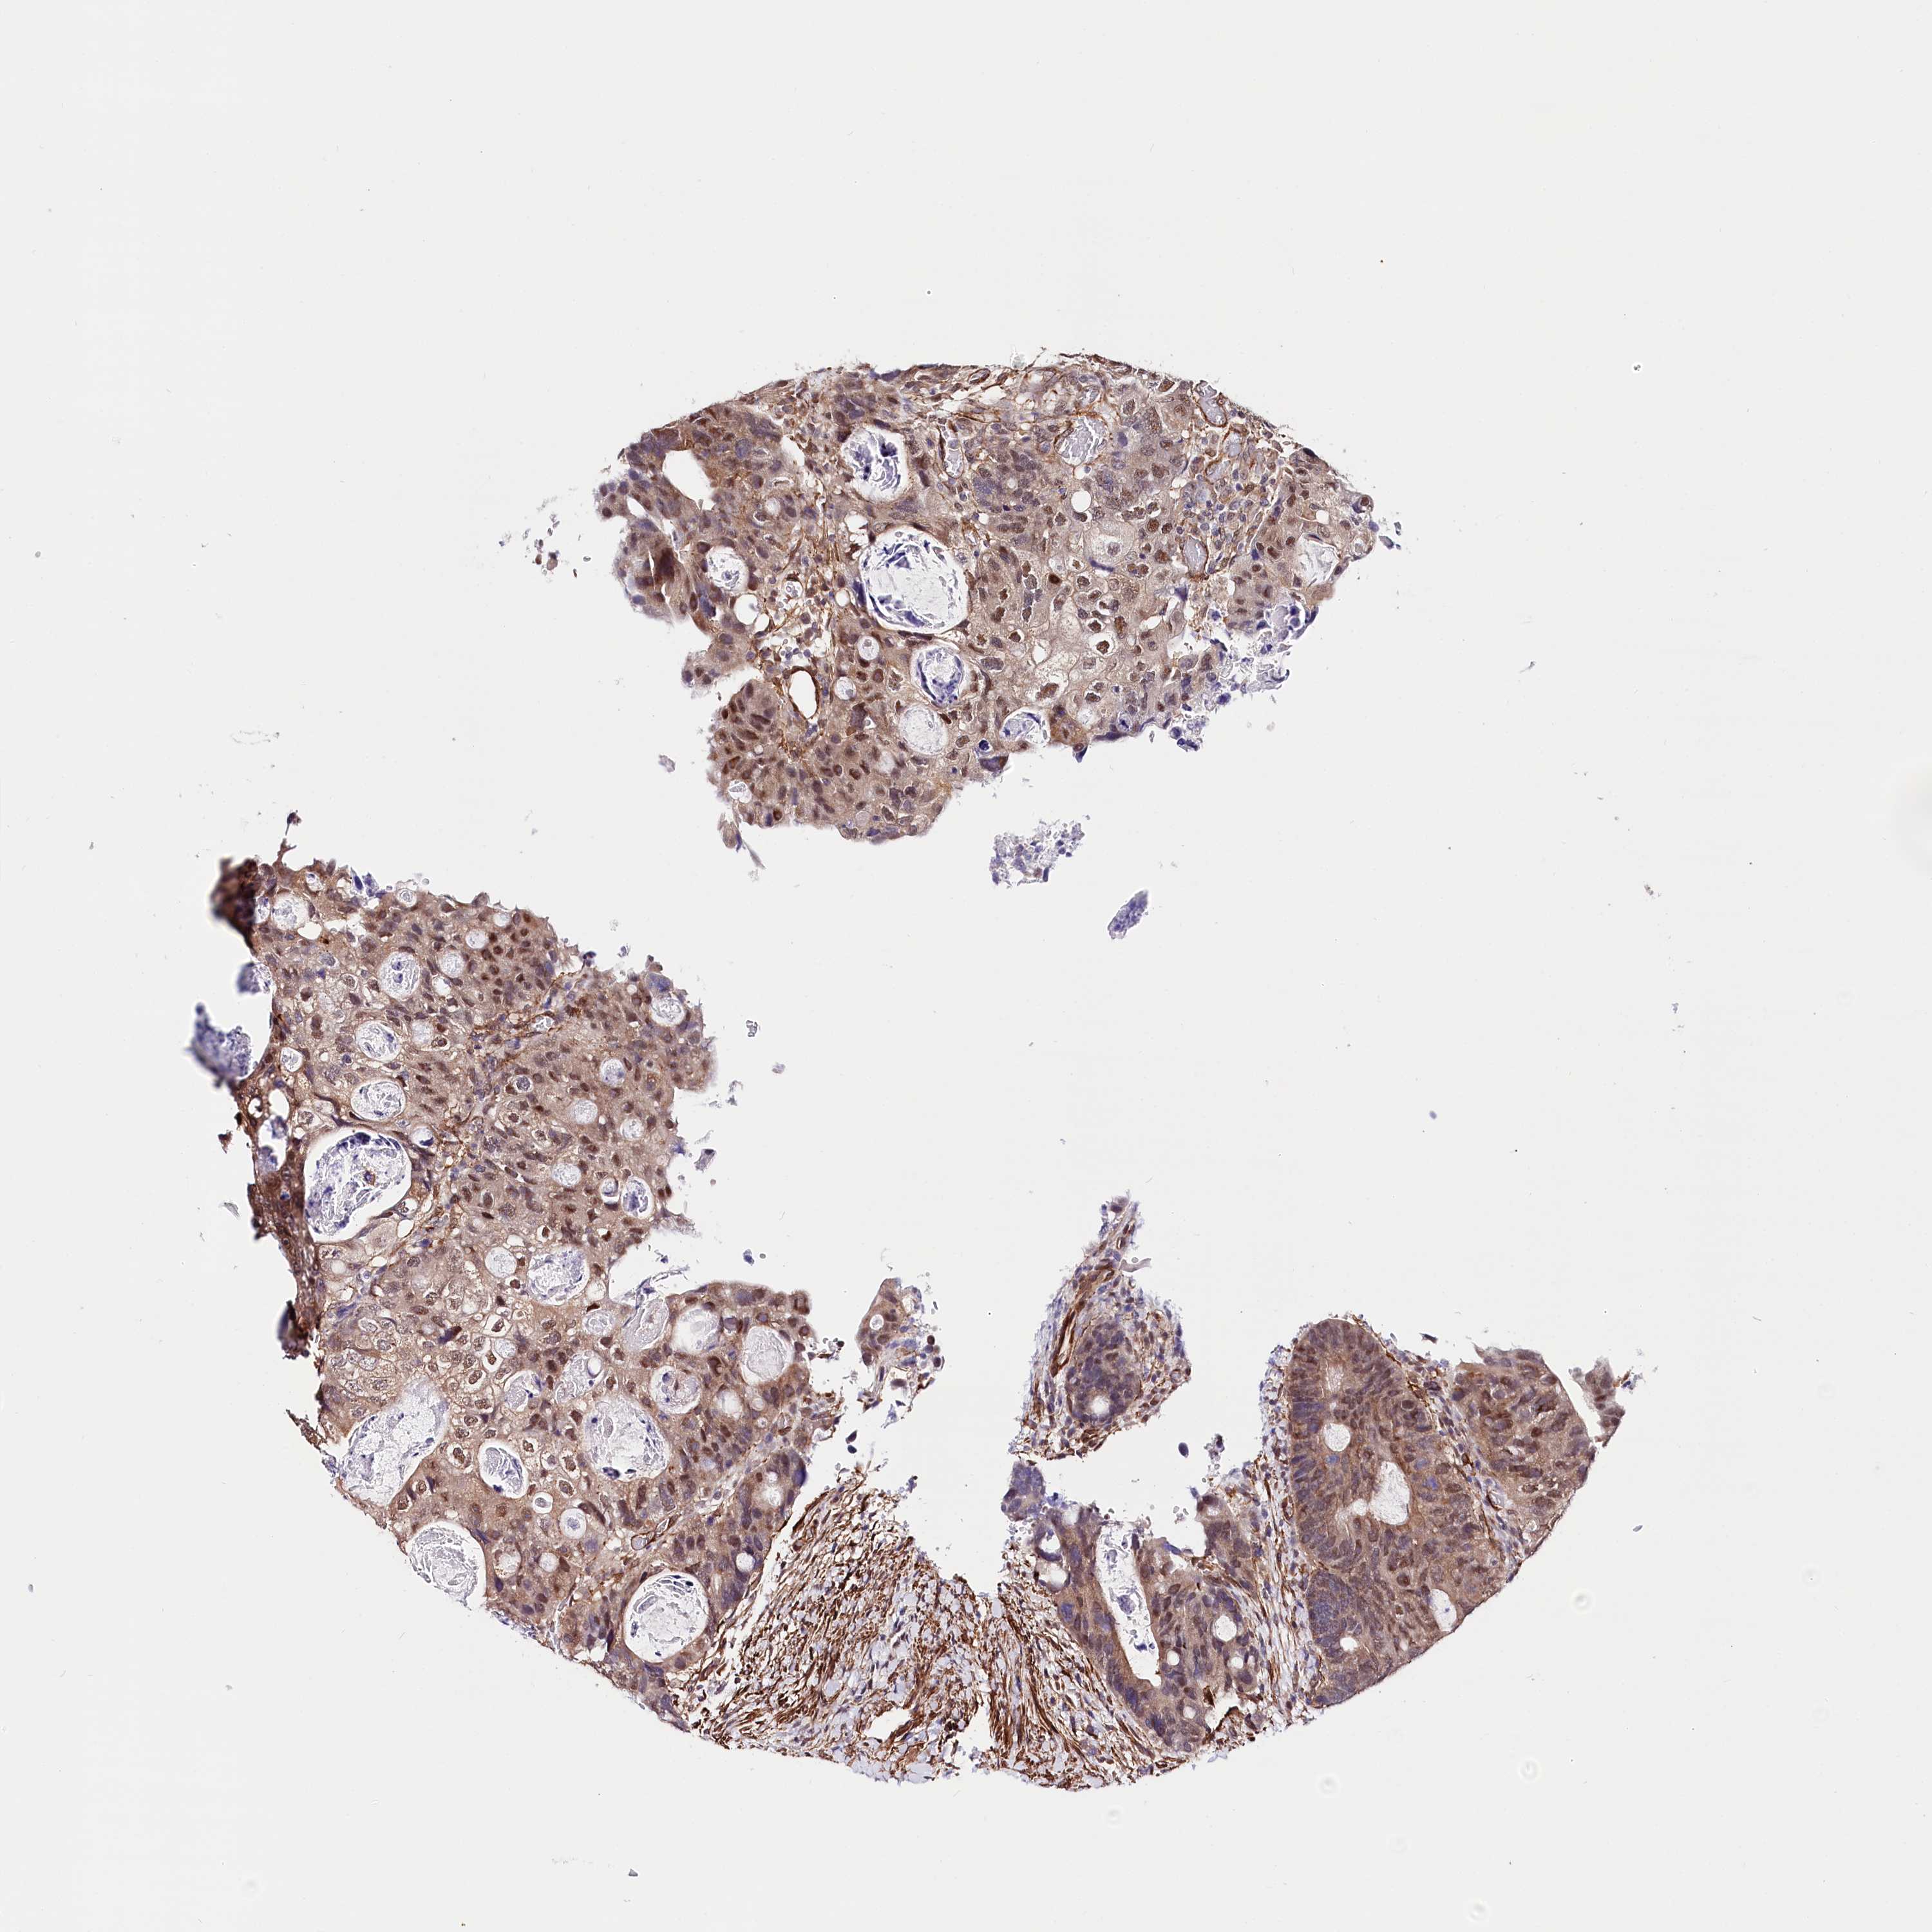

Colorectal cancer

Rectum adenocarcinoma

Average pTPM 13.9

Number of samples 486